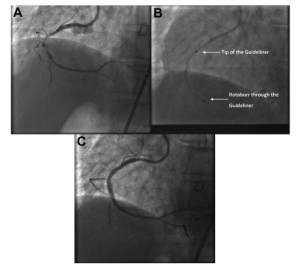

She was referred for percutaneous coronary intervention (PCI) to treat a tight, heavily calcified stenosis in the mid-segment of the right coronary artery (Figure 1A).

A previous PCI attempt had failed because the 1.25-mm rotational atherectomy burr could not cross the calcified lesion (Figure 1B).

A 6-French GuideLiner catheter was then advanced using the “mother-and-child” technique proximal to the stenosis (Figure 1B).

PCI was completed using standard techniques, achieving excellent angiographic results (Figure 1C).